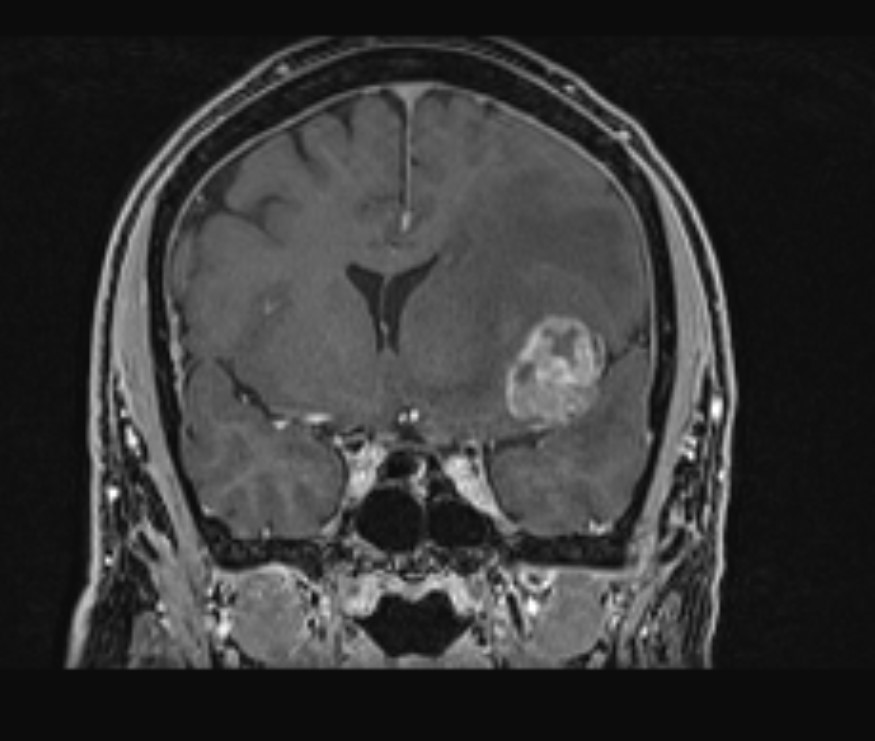

Το δόγμα της σύγχρονης χειρουργικής όγκων απεικονίζεται στις μαγνητικές αυτές. Στόχος μας είναι η μέγιστη δυνατή ασφαλής αφαίρεση του όγκου. Δεν πρέπει να στοχεύουμε στην εξαίρεση όχι μόνο του όγκου, όπως φαίνεται στην μαγνητική αλλά και στην αφαίρεση και της διηθητικής ζώνης και της υγιούς περιβάλλουσας περιοχής αν αυτή δεν έχει λειτουργίες. Η εικόνα 1α είναι προεγχειρητική, εδώ έχει σχεδιασθεί το εύρος της στοχευμένης εξαίρεσης. Η εικόνα 1β δείχνει το μετεγχειρητικό αποτέλεσμα μιας υπερολικής εξαίρεσης. Πρόκειται για την πρώτη ασθενή που χειρουργήθηκε στην Ελλάδα από τον Καθ. Γούσια τον Οκτώβριο του 2023, η οποία διαγνώσθηκε με την πιο επιθετική μορφή του γλοιοβλαστώματος, το λεγόμενο γλοιοσάρκωμα, η οποία 20 μήνες μετά την χειρουργική επέμβαση παραμένει χωρίς ένδειξη όγκου στην μαγνητική και το πιο σημαντικό χωρίς νευρολογικά ελλείμματα.